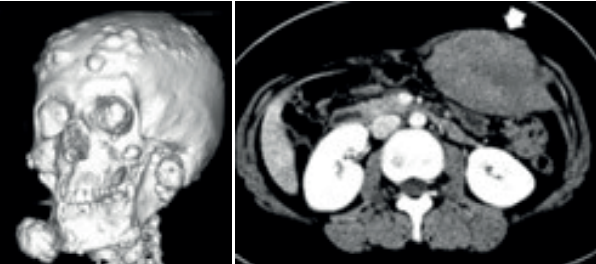

- Manifestações Extracólicas (Síndrome de Gardner): A mutação no gene APC também predispõe a crescimentos anormais em outros tecidos.

- Osteomas (mandíbula).

- Hipertrofia congênita do epitélio pigmentar da retina (CHRPE).